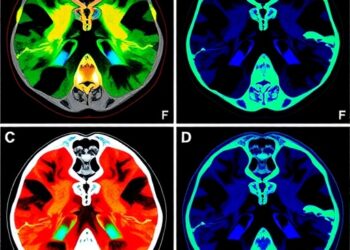

- Visualization of a LAG3 Interaction Network: The study reveals a detailed network of interactions between MHC class II and LAG3, uncovering multiple novel drug targets and signaling mechanisms. This comprehensive “molecular blueprint” provides a deeper understanding of how LAG3 modulates immune responses and its potential impact on therapeutic interventions.